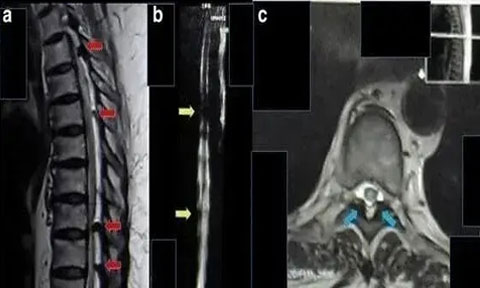

2017 年海外報道一例 62 歲的印尼籍婦女,被診斷為胸部截癱、慢性腎功能衰竭、糖尿病,慢性腎功能衰竭 2 年,肌酐水平為 11 mg/dL,無小便。采用間充質(zhì)干細(xì)胞移植方案治療,鞘內(nèi)注射和靜脈注射后三周后,患者可以移動腳趾,腎功能得到改善。肌酐水平降至 9 mg/dL。8 個月后,患者可以抬起腿,肌酐水平是 2mg/dL,小便恢復(fù)正常。